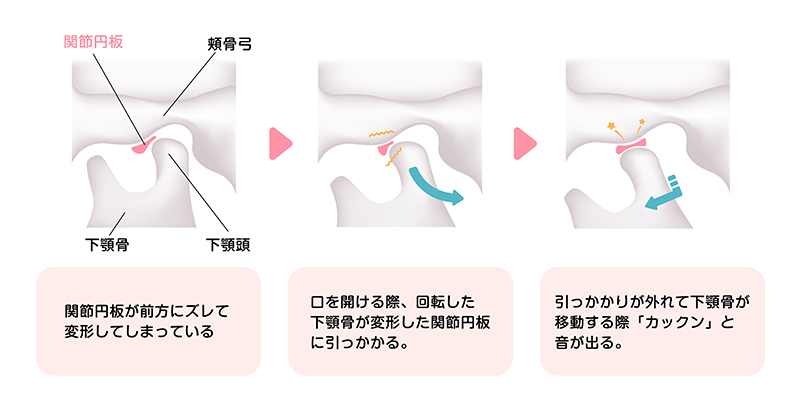

顎関節症は顎の痛みだけでなく、頭痛や肩こりなどの症状へ広がってしまうこともあります。自覚症状のある方は早めの受診をおすすめします。

かみ合わせがずれることにより、下顎が正常に運動せず顎骨や下顎頭もずれてしまい、顎の開閉の障害となります。正常なかみ合わせの形成が顎関節症治療の第一歩です。

ストレスは筋肉の緊張を生み、歯ぎしり・食いしばりにつながります。歯ぎしりや食いしばりは顎関節や筋肉に大きな負荷をかけてしまうため、顎関節症を引き起こす要因となります。

日常的に歯ぎしりや食いしばりをする、頬杖をつく、うつぶせ寝をする等といった癖は、顎関節や筋肉に過剰に負担をかけてしまい、顎関節症を発症させる恐れがあります。

マウスピースを就寝時に装着することにより睡眠時の歯ぎしりや食いしばりを抑制し、顎関節にかかる負担を緩和・軽減していきます。